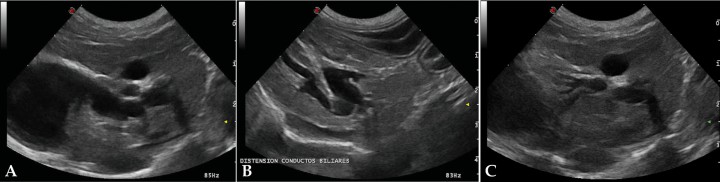

La ecografía hepática mostro un hígado de pequeño tamaño, con presencia de focos hiperecoicos y con sombra acústica (Fig. 2). Los conductos biliares mostraban distensión severa y aspecto tortuoso, manteniendo su comunicación con la vesícula biliar, sin evidencia de obstrucción en algún punto concreto de su recorrido (Fig. 3). La papila duodenal se visualizaba normal. La vena porta presentaba pequeño tamaño, flujo hepatópeto y velocidad aparentemente reducida (Fig. 4). Se evidenció la presencia de múltiples vasos de aspecto tortuoso adyacentes al riñón izquierdo (Fig. 5). Ambos riñones presentan múltiples infartos renales y focos mineralizados en la corteza, sedimento con sombra acústica en pelvis renal izquierda y presencia de cálculos en riñón derecho (Fig. 6). Pequeña cantidad de líquido libre anecoico (Fig. 7).

<p>(A) Cortes longitudinales de hígado parasagitales y oblicuos derechos. Se observa dilatación de los conductos biliares intrahepáticos y conducto cístico, así como la relación con la vesícula biliar (B y C) Conductos biliares dilatados.</p>

Figura 3

(A) Cortes longitudinales de hígado parasagitales y oblicuos derechos. Se observa dilatación de los conductos biliares intrahepáticos y conducto cístico, así como la relación con la vesícula biliar (B y C) Conductos biliares dilatados.